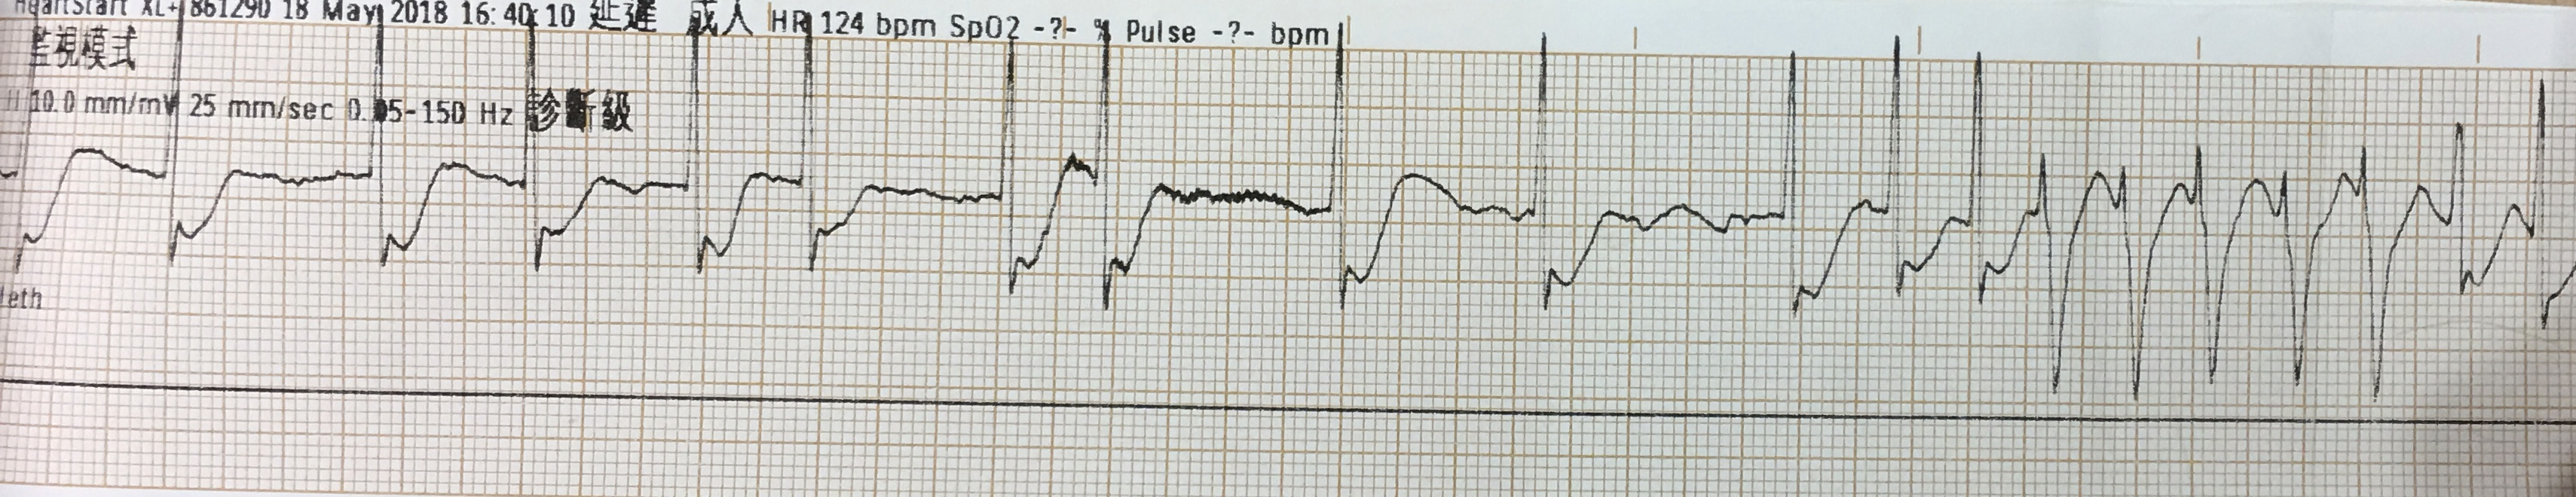

CPR兩分鐘後,看了一下ECG monitor的rhythm

嗯......有點像TdP?還是Vf?

⚡️不管如何病患還是不穩定的狀態,繼續電擊200J,然後CPR、給藥

Rate:102 bpm

Rhythm:看不到哪裡有明顯P wave

Axis:RAD

Interval:QTc算起來469 ms

Ischemia:看起來是aVR STE with multiple leads STD的subendocardial ischemia pattern

這在剛剛急救然後ROSC的病患,並不少見。因為整體coronary a.處於hypoperfusion狀況,另外也打了不少的epinephrine,這也會讓coronary a.血管收縮。

這種ECG pattern可能呈現的原因是因為diffuse subendocardial ischemia or oxygen supply/demand mismatch➡此ECG並不具有specific for AMI,只能簡單表示目前心臟目前正處於嚴重廣泛整體供需不平衡,但原因不明